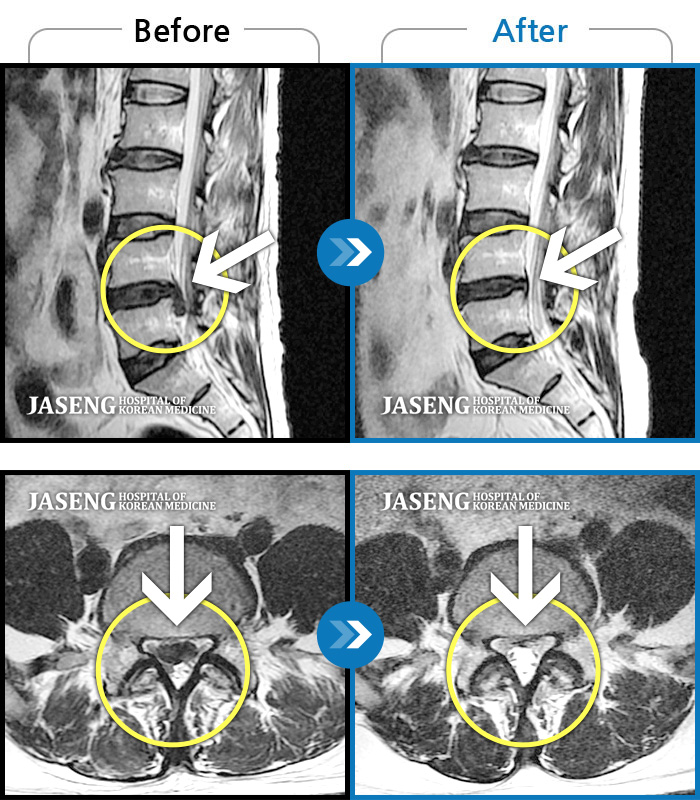

허리디스크

일산 · 김태용 원장

허리와 좌측 하지 방사통이 심하시어 보행이 거의 힘들었다.

촬영시기

2021.03.06 ~ 2021.07.15

2021.07.23